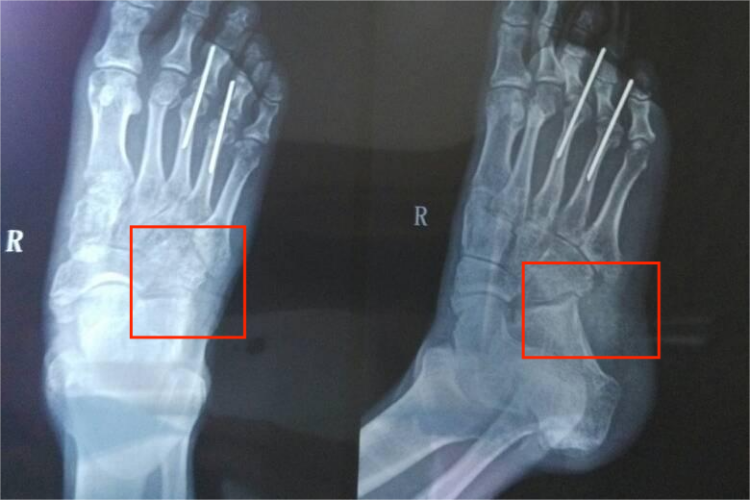

X线摄片检查见骰骨后外缘撕裂骨折,骨折片轻度分离移位。或可见骰骨体积变小,密度增高,呈压缩性骨折,严重者常伴关节面塌陷或骰骨外侧柱缩短。

右骰骨骨折患者应立即就诊,并在医生指导下进行治疗。无移位的右骰骨撕脱骨折及轻度压缩骨折可用小腿石膏固定治疗。严重压缩骨折须手术恢复骰骨外形,采取从骰骨中间撑开后植骨,用外固定器或钢板固定。

骨折粉碎严重需行关节融合术。完全脱位应尽早复位,以解除对皮肤的压迫。如复位失败应切开复位,并用克氏针或微型钢板固定。术后用石膏托固定6周,拔除克氏针后练习活动。